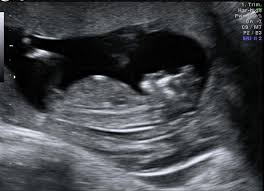

This patient comes in for routine NT screening

What is anencephaly?